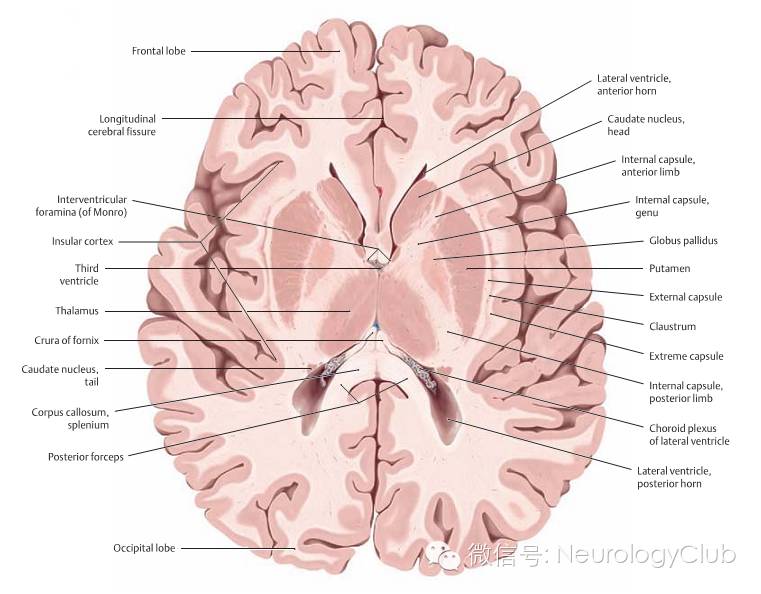

(图4:基底节区解剖示意图。引自:Head and Neuroanatomy.Thieme Medical Publishers Inc;1st ed. 2010)